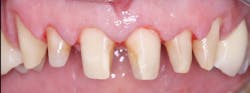

Figure 5: Patient had moderate postoperative pain after tooth preparation appointment.

Figure 6: Patient had almost no postoperative pain after tooth preparation appointment. Both patients in Figures 5 and 6 had same apparent trauma during tooth preparation, but they reported very dissimilar postoperative pain.